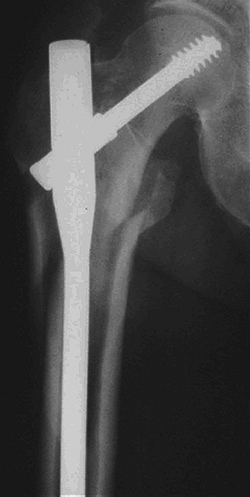

This implant combines the features of a sliding hip screw (SHS) and an intramedullary nail (Fig. 30.6).

Figure 30.6. Reverse obliquity fracture stabilized with a cephalomedullary nail.(From Bucholz RW, Heckman JD, Court-Brown C, et al., eds. Rockwood and Green’s Fractures in Adults, 6th ed. Philadelphia: Lippincott Williams & Wilkins, 2006.) -

Use of intramedullary hip screws has been

most effective in intertrochanteric fractures with subtrochanteric

extension and in reverse obliquity fractures. -